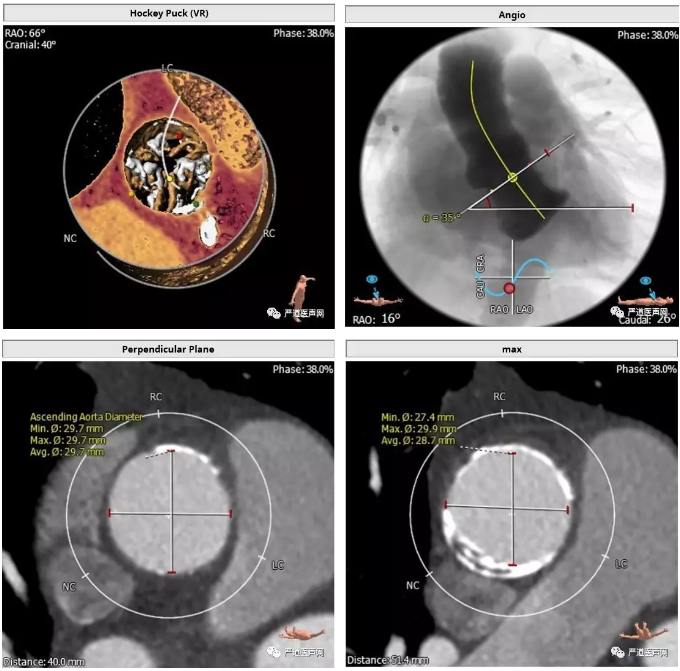

>>主动脉根部解剖:

三叶瓣,中度钙化,窦部结构尚可,冠状动脉高度尚可(LCA 16.7mm,RCA 14.8mm)。升主动脉弥漫性钙化,升主动脉高度40-50mm血管壁大量钙化并钙化中夹杂血栓,血管夹层风险较高。

根据患者术前 CT分析,这个病人瓣上 40-50mm 处主动脉弥漫性钙化,类似瓷化主动脉弓,钙化中夹有血栓,操作过程中主动脉夹层发生风险高。经术前讨论结合患者左室流出道解剖结构选择低位释放,规避升主动脉夹层风险,同时利用病人特有生理解剖结构规避术后瓣周漏的发生。同时根据四肢血管CT,选择右股动脉为主路径,选择 L29 规格VenusA-Valve 瓣膜。